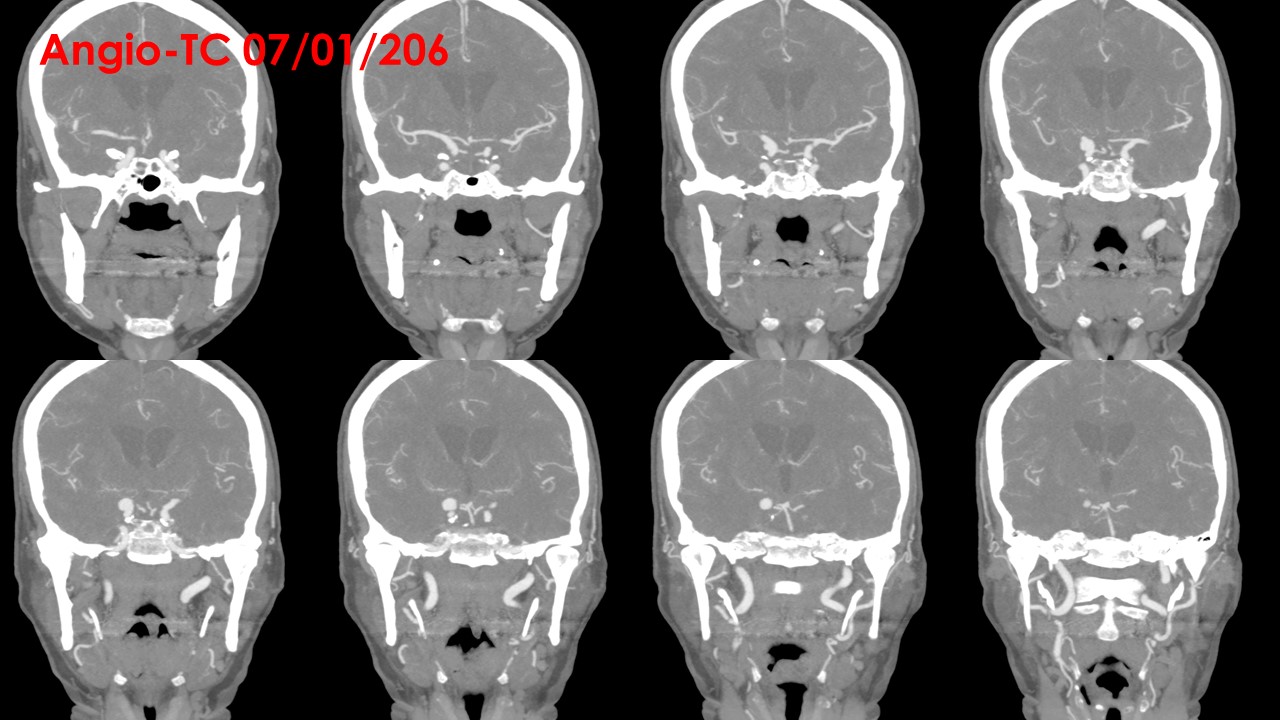

ANGIO TC:

Troncos supraorticos permeables, sin variantes anatómicas reseñables.

Origen fetal de ambas arterias cerebrales posteriores.

A nivel de la arteria carótida supraclinoidea derecha, entre la salida del ACoP (ACP) ipsilateral y la ACA derecha se observa una imagen de adición opacificada de aspecto nodular, de aproximadamente 11 mm x 8 mm, compatible con aneurisma, probablemente responsable de la hemorragia actual. A nivel de la arteria carótida supraclinoidea izquierda se observa otra imagen de características similares de 7 mm x 4.5 mm, compatible con aneurisma de dicha arteria.

No se visualizan otras dilataciones aneurismáticas a nivel intracraneal.

No se observan estenosis valorables en sistema arterial intra ni extracraneal.